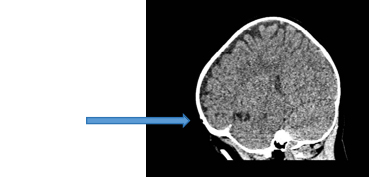

图9:手术中内镜系统下所见肿物以及肿物完全切除后局部颅骨的凹陷。